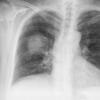

Case 3 RM & UL pneum PA

Date: 07/04/2004

Views: 5884